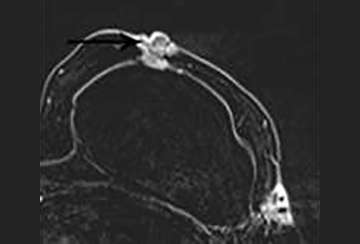

The normal appearance following mastectomy is dependent on the type of reconstruction techniques include autologous tissue flaps and implant reconstruction. Autologous tissue flaps include the transverse abdominis myocutaneous (TRAM) and deep inferior epigastric perforator (DIEP) flaps, although numerous other techniques exist. In general, post-surgical changes such as seromas and fat necrosis will also be encountered following mastectomy as in breast conservation surgery. Recurrences are most common in the anterolateral breast and axilla, where residual breast tissue may remain (Figure 6)6,7.